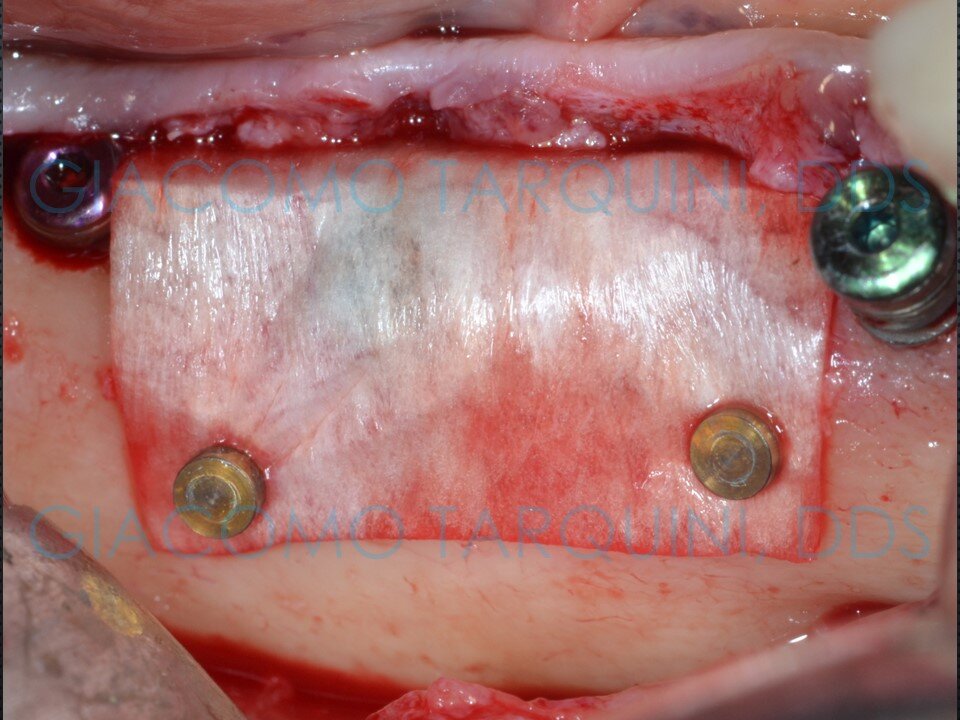

- Eseguire il protocollo rigenerativo di scelta (ad es. mediante membrane di tipo riassorbibile o non riassorbibile)

CASO CLINICO

Il caso clinico illustra il trattamento chirurgico-rigenerativo di un impianto endosseo affetto da peri-implantite effettuato secondo il protocollo «PIEZOCLEAN by Dr. Giacomo Tarquini»